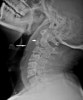

X-ray : 경추 골절(Fractures of the Cervical spine)

AP, lateral, open-mouth view를 모두 찍습니다(C2). 다발성 손상환자에서 가장 중요한 X-ray는 C1~T1까지 다 볼 수 있는 cross-table view X-ray 사진입니다. 대부분 CT나 MRI도 필요합니다.

가장 잘 놓치는 손상 부위는 상부 및 하부 목뼈부위 손상이므로 lateral X-ray에서는 위로는 후두부, 밑으로는 T1까지 촬영하여야 합니다. 가끔 목뼈-등뼈 연결부위를 보기 위해 수영면(swimmer's view) 영상을 필요로 하지만, 대개 이 부위는 CT나 MRI로 평가합니다.

Lateral X-ray에서는 목 앞쪽 연부조직의 종창, 추체 높이와 정렬, 후관절과 가시돌기 등을 관찰합니다. Open mouth X-ray 사진에서는 치돌기 골절, C1 손상, 후두돌기의 위치를 관찰하여야 합니다. AP view에서는 후관절 골절이나 탈구로 인한 극돌기의 미세한 부정렬을 볼 수 있습니다.